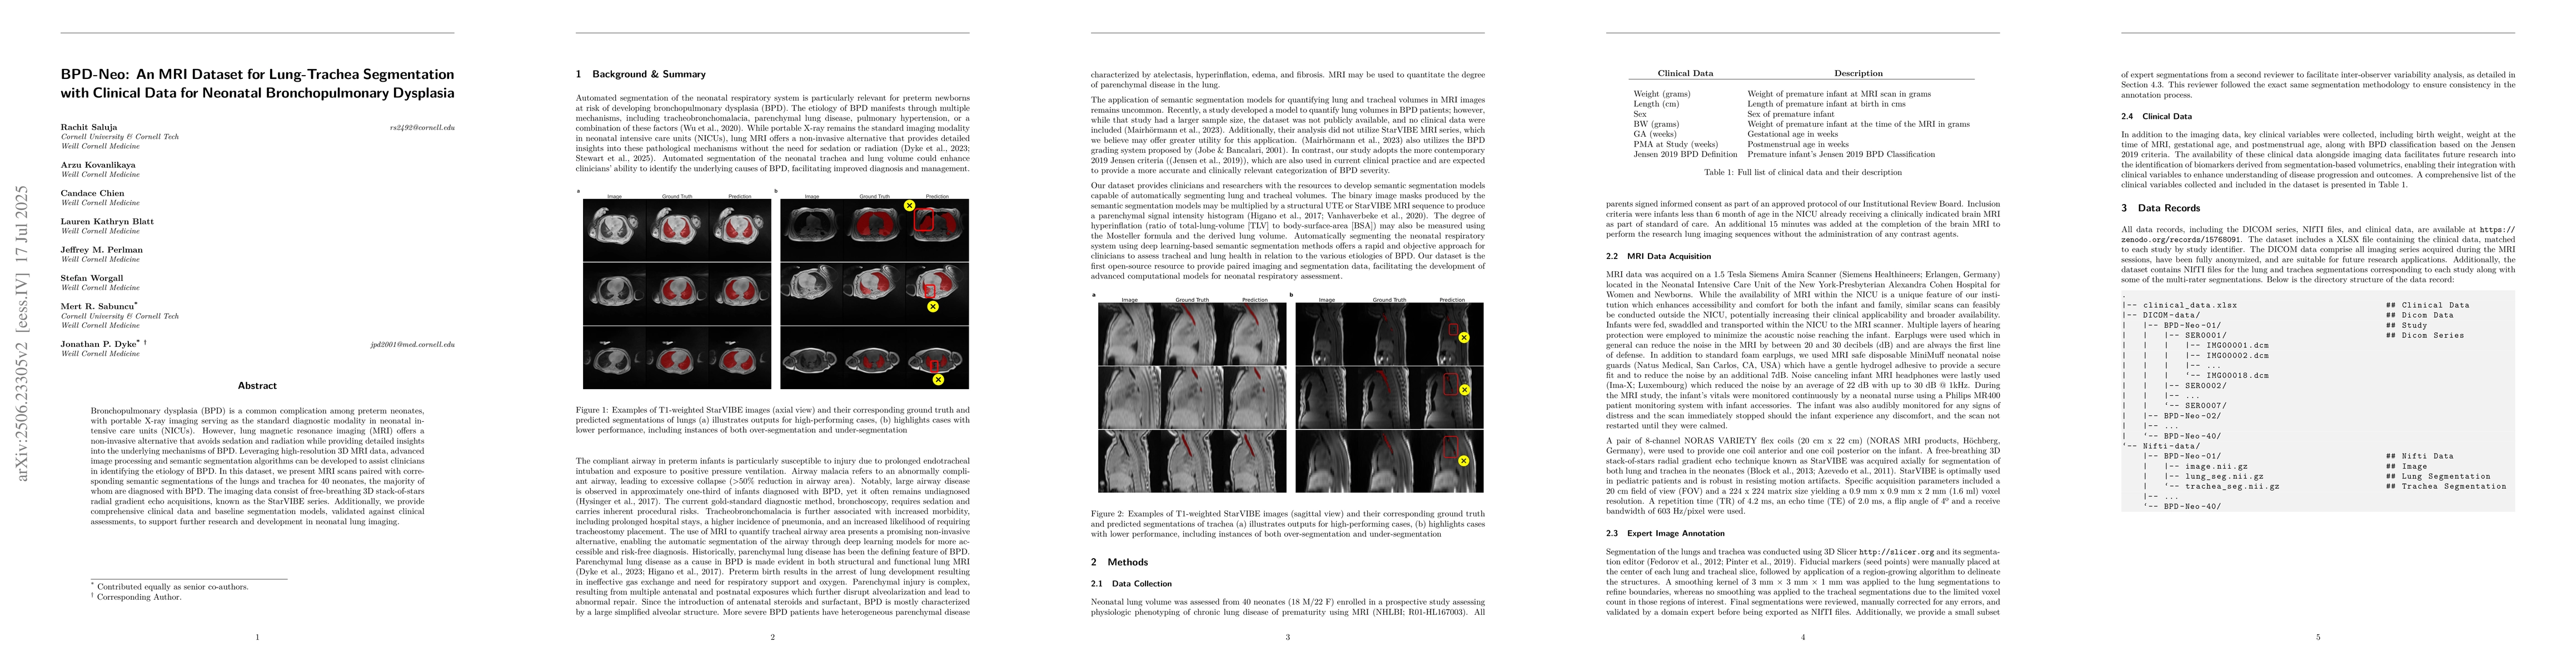

Bronchopulmonary dysplasia (BPD) is a common complication among preterm neonates, with portable X-ray imaging serving as the standard diagnostic modality in neonatal intensive care units (NICUs). However, lung magnetic resonance imaging (MRI) offers a non-invasive alternative that avoids sedation and radiation while providing detailed insights into the underlying mechanisms of BPD. Leveraging high-resolution 3D MRI data, advanced image processing and semantic segmentation algorithms can be developed to assist clinicians in identifying the etiology of BPD. In this dataset, we present MRI scans paired with corresponding semantic segmentations of the lungs and trachea for 40 neonates, the majority of whom are diagnosed with BPD. The imaging data consist of free-breathing 3D stack-of-stars radial gradient echo acquisitions, known as the StarVIBE series. Additionally, we provide comprehensive clinical data and baseline segmentation models, validated against clinical assessments, to support further research and development in neonatal lung imaging.

A deep learning-based approach was used to segment neonatal lung images, leveraging the U-Net architecture with self-configuring methods for biomedical image segmentation.